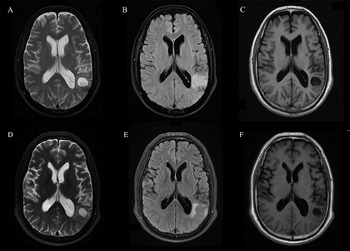

The routine laboratory blood tests, including eosinophil and lymphocyte count, were completely normal apart from the elevated inflammation markers (C-reactive protein and neutrophil count). Schistosomes, Clonorchis sinensis, Echinococcus granulosus and Toxoplasma gondii antibodies were negative in his serum, as were Cryptococcus capsular antigen and next-generation sequencing results from cerebrospinal fluid. Multiple intracranial nodules affecting the supratentorial and infratentorial cerebral parenchyma were shown in detail on CT and MRI of the head, indicating possible intracranial parasitic infection (Fig. 1). Ultrasound scan confirmed the presence of 2 palpable and soft masses located in muscles, which were approximately 19 × 8 × 15 mm3 under the right chest wall and 26 × 10 × 19 mm3 under the right midaxillary line (Fig. 2). A subsequent biopsy of the mass (Fig. 3) showed larval-like tissue, peripheral fibrous tissue hyperplasia, lymphocytic infiltration and hyaline degeneration. The patient was probably diagnosed with taeniasis and cysticercosis and treated with oral albendazole (400 mg, twice daily) over 2 weeks. Hydrocortisone 50 mg was provided 2 days after the first albendazole treatment to counteract any potential negative effects on the central nervous system. After only 2 days of this antiparasitic treatment, the adult tapeworm was eliminated through the patient's feces (Fig. 3). When compared with the first MRI (half a month before antiparasitic treatment), the second MRI (half a month after antiparasitic treatment) demonstrated a slightly smaller focus (Fig. 1). The headache and vomiting resolved, and the patient remained symptom free over a 3-month follow-up period.

Fig. 2. Ultrasound scan shows hypoechoic mass containing cysticercus with calcification in the muscles of (A, B) right anterior thoracic wall (19 × 8 × 15 mm3) and (C, D) right midaxillary line (26 × 10 × 19 mm3).